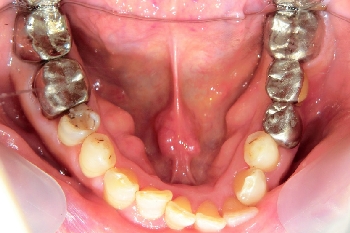

東京都足立区 K.T様 右下567番 メタルボンドブリッジ修復

担当歯科医師:川津良介理事長